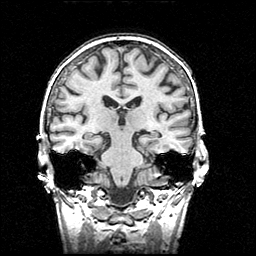

MR Study #1 -- Slice #57

[Home][Help][Clinical] Slice 57